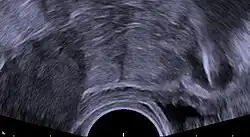

Transvaginal ultrasonography showing a perforated copper IUD as a hyperechoic (rendered as bright) line at right, 30 mm (1.2 in) away from the uterus at left. The IUD is surrounded by a hypoechoic (dark) foreign-body granuloma.

Regardless of IUD type, there are some potential side effects that are similar for all IUDs. Some of these side effects include bleeding pattern changes, expulsion, pelvic inflammatory disease (especially in the first 21 days after insertion), and rarely uterine perforation. A small probability of pregnancy remains after IUD insertion, and when it occurs there is a relatively high risk of ectopic pregnancy.[2] Rates of expulsion after delivery depend on how soon the device is placed following delivery, the type of IUD, and the method of delivery with within 3 days, hormonal IUDs, and vaginal delivery associated with a higher risk.[45]